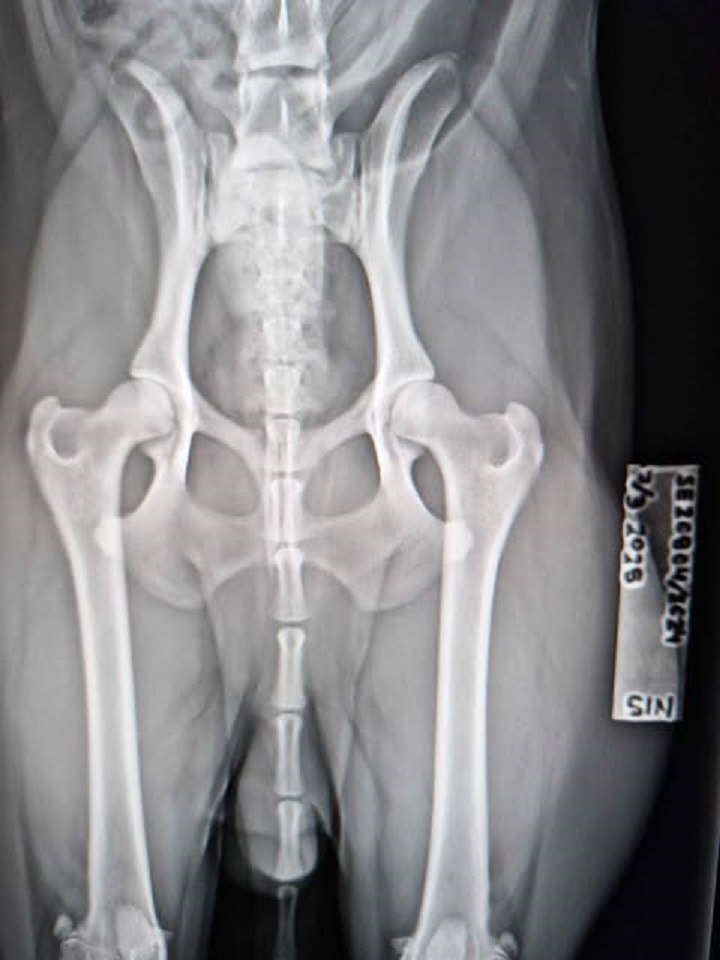

"Tott"